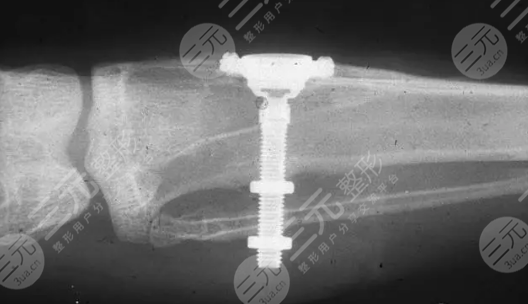

国产的种植牙要多少钱一个

在正常情况下来说,进行一科国产种植牙的价格大概是在5000元到三万元之间不等,但是的价格是没有办法进行固定的,会根据许多外界的因素而导致价格有这非常大的波动,以下几个因素就是影响到价格最主要的原因。